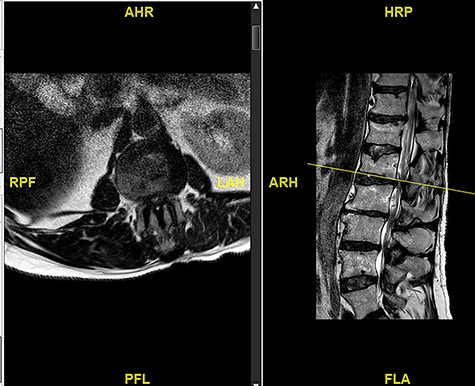

A 56-year-old male patient lumber decompression in a local neurosurgical centre for severe canal stenosis at L1/2 and L2/3 (Fig. 1) level after presenting with bilateral leg weakness and perianal numbness. Three months later he presented with recurrence of right leg pain radiating into the calf and worsening back pain as well as distal lower limbs weakness bilaterally with no sphincter problem. Following an magnetic resonance induction (MRI), which revealed a disc prolapse at L1/2 (Fig. 2), the patient was referred to our Centre. The images were reviewed by a consultant radiologist and as a possibly of intradural herniated disc disease was described. Intraoperatively no extradural disc prolapse was found, so midline durotomy was performed. Intradural disc herniation (IDH) was identified, which was communicating with the disc space through a midline defect in anterior dura (Fig. 3). This was removed extracted under the microscope. Post-operatively, he had a CSF leak needing re-suturing of dura. The patient did make a good post-operative recovery with no major sensory or motor deficits or sphincter disturbance.

Initial MRI images prior to index procedure revealing stenosis at L1/2 and L2/3.